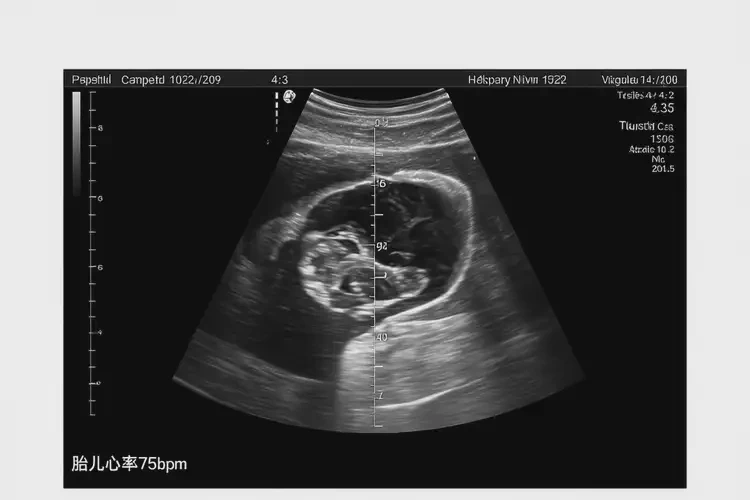

懷孕10周胎心率75怎么回事(圖1)

懷孕10周胎心率75怎么回事

胎心率75次/分鐘在懷孕10周時明顯偏低。正常情況下,懷孕10周的胎心率應(yīng)在140-170次/分鐘之間。胎心率低于120次/分鐘可能提示胎兒存在異常情況,需要引起重視。